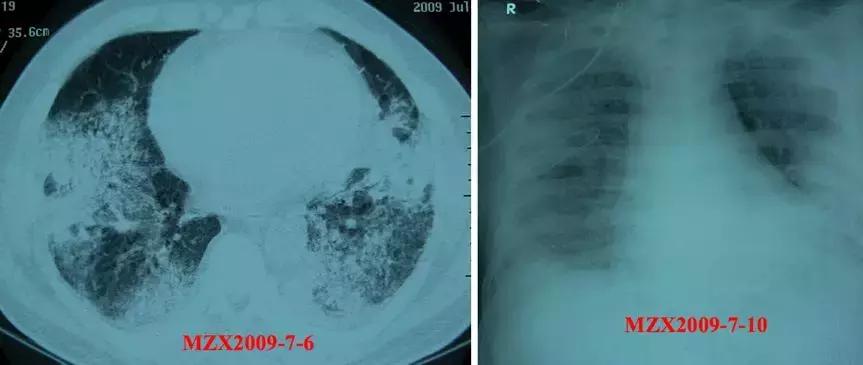

57y,M,糖尿病史;咳嗽、咳痰2月,加重伴气短、发热2周。广谱抗细菌、真菌治疗无效。

影像学

好像似是而非,主治医生按机化性肺炎进行治疗了,09/07/2009:甲强龙,80mg iv bid x 3,2009年7月14日复查胸片,影像似有部分吸收,效果还不错。

但是很快病情加重,胸片渗出增加,这时痰抗酸杆菌呈阳性发现,可见不是机化性肺炎。